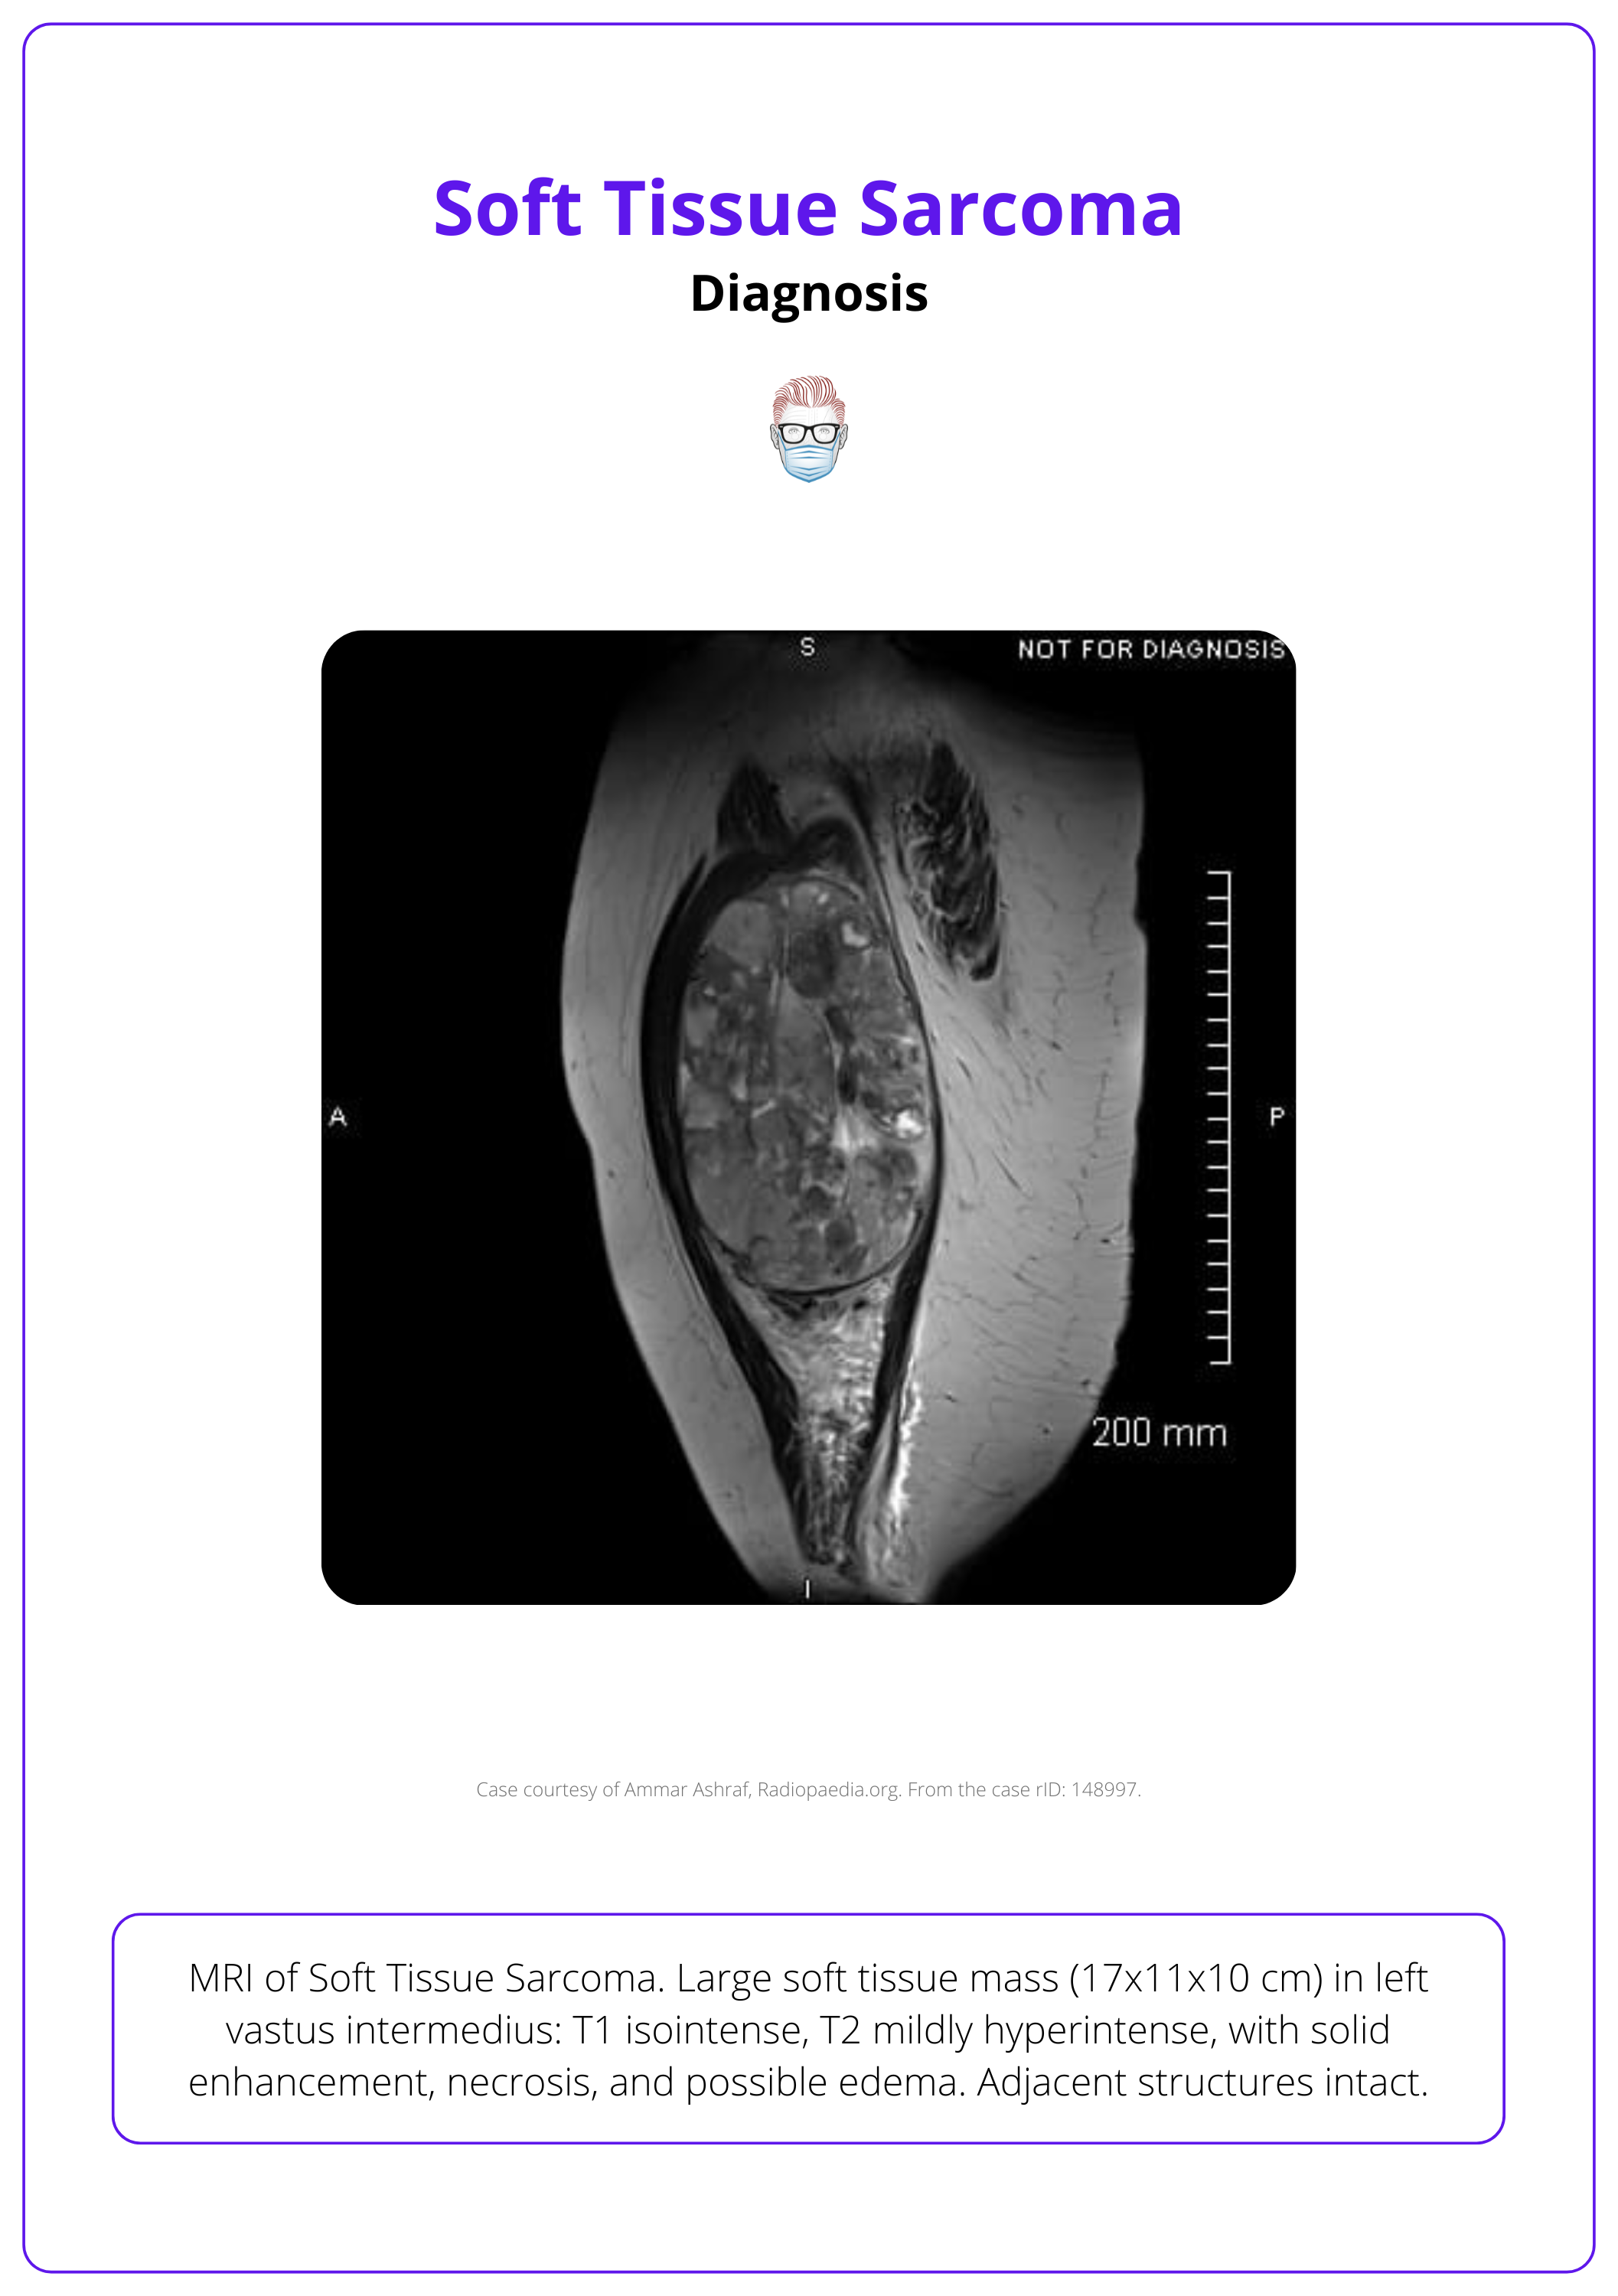

The image below illustrates an MRI image of a soft tissue sarcoma.

Imaging

- MRI: rimary imaging modality for tumors in the extremities, pelvis, and trunk.

- CT: Important for assessing calcified lesions, pleuropulmonary, and retroperitoneal sarcomas, with comparable effectiveness to MRI.

- Ultrasound: May serve as initial imaging but should lead to CT or MRI if soft tissue sarcoma is suspected.